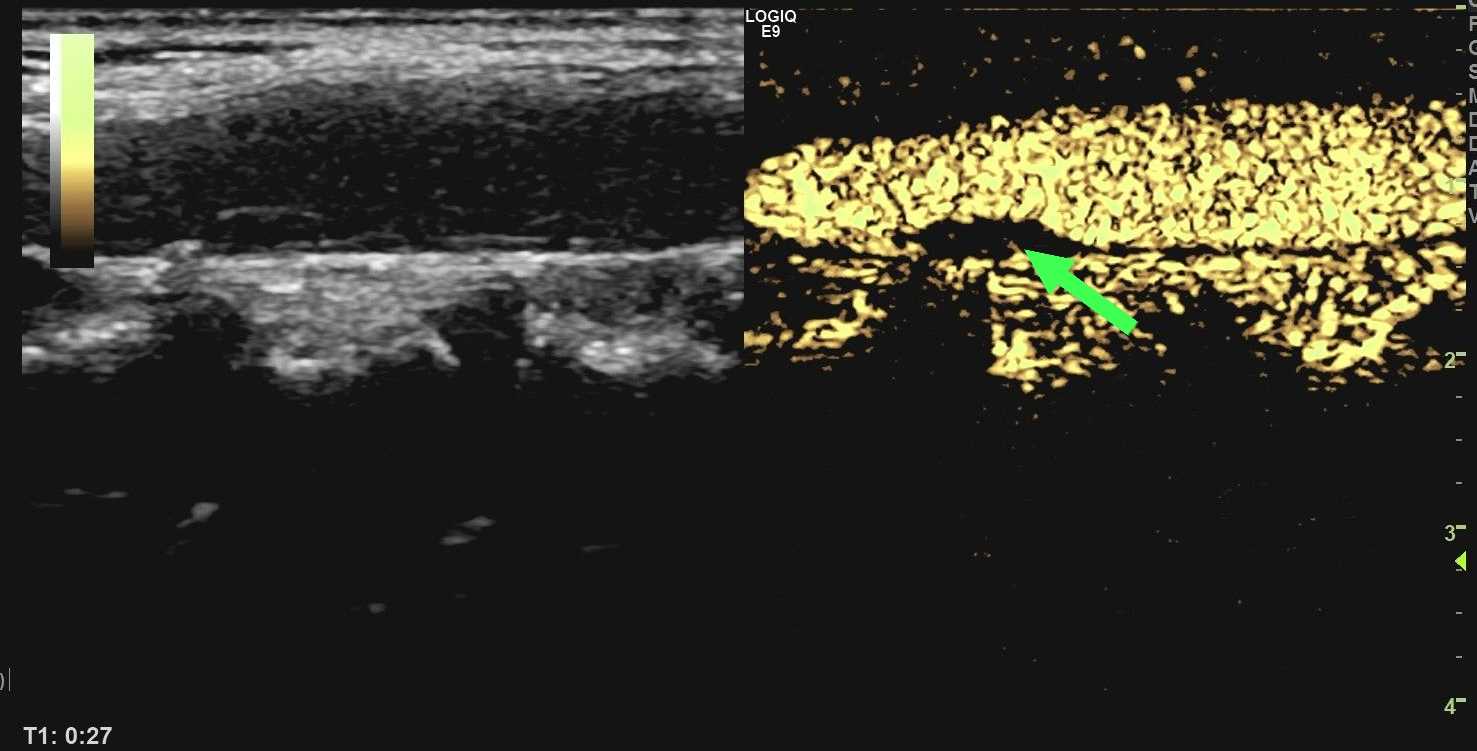

根据超声造影增强情况对斑块内新生血管进行半定量评估:0分(斑块中没有造影剂信号),1分(斑块中点状造影剂信号),2分(介于1~3分之间,斑块内可见到点状和1~2支短线状增强),3分(斑块中有多发的线状造影剂信号)。见图1图2

Figure 1. The enhancement within plaques in the diabetic group

1. 糖尿病组斑块内增强情况

Figure 2. The enhancement within plaques in the non-diabetic group

2. 非糖尿病组斑块内增强情况